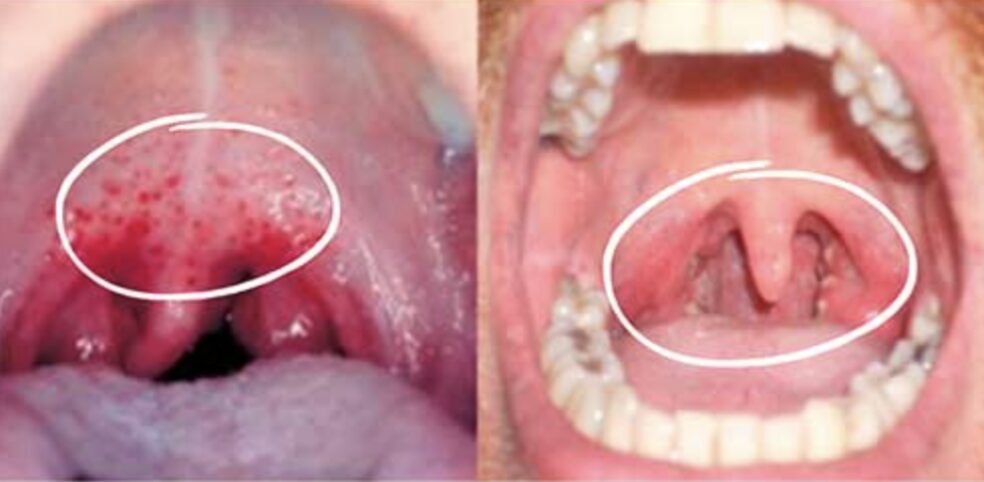

【写真】咽頭淋病による咽頭炎

<参考>

https://stdcenterny.com/articles/std-sore-throat.html